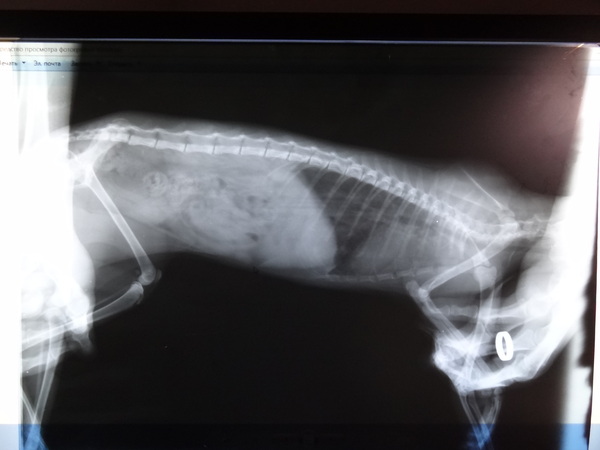

Ветеринары Пикабу помогите вылечить кошку!

Пару месяцев назад друзья нашли кошку на улице в дождь, она кашляла и чихала, были выделения из глаз и носа. Её лечили месяц:

- гемовит 3 дня

- сульфитристан 4 дня

- капли максидин флакон

И я её забрала себе, долечила глазки, ей стало лучше, почти перестала кашлять.

Но спустя пару недель опять начала. Мы пошли к ветеринару:

- Сироп от кашля Проспан 10 дней

- Укол Бициллин-3

Трис стало стало лучше.

Прошло пара недель и она опять кашляет! Не каждый день (или я не вижу), но кашляет! Когда гладишь по шее (даже несильно) или про всяких побегушках.

Ест хорошо, довольно активна.

Несколько раз был стул с кровью (под конец приёма Проспана).

Вот так это выглядит: https://youtu.be/hSks9Jc2Q5A

Почему я не иду к ветеринару ещё раз? Потому что нет денег на два дорогущих анализа на хладимиоз и микоплазмоз, который ещё говорят сделать. Я боюсь что с меня просто хотят вытянуть кучу бабла, так как пытались заставить оплатить счет с неправильной калькуляцией. А предыдущий ветеринар не помог и как-то был пофигистичен. Я не уверена в адекватности ветеринаров, к которым я попадаю.

Заранее благодарю лигу ветеринаров!

Трис хорошая кошка, она ходит только в лоток и любят когда её гладят. Ещё она любит гоняться за мышами, которые я ей кидаю как собаке, жаль не приносит обратно.